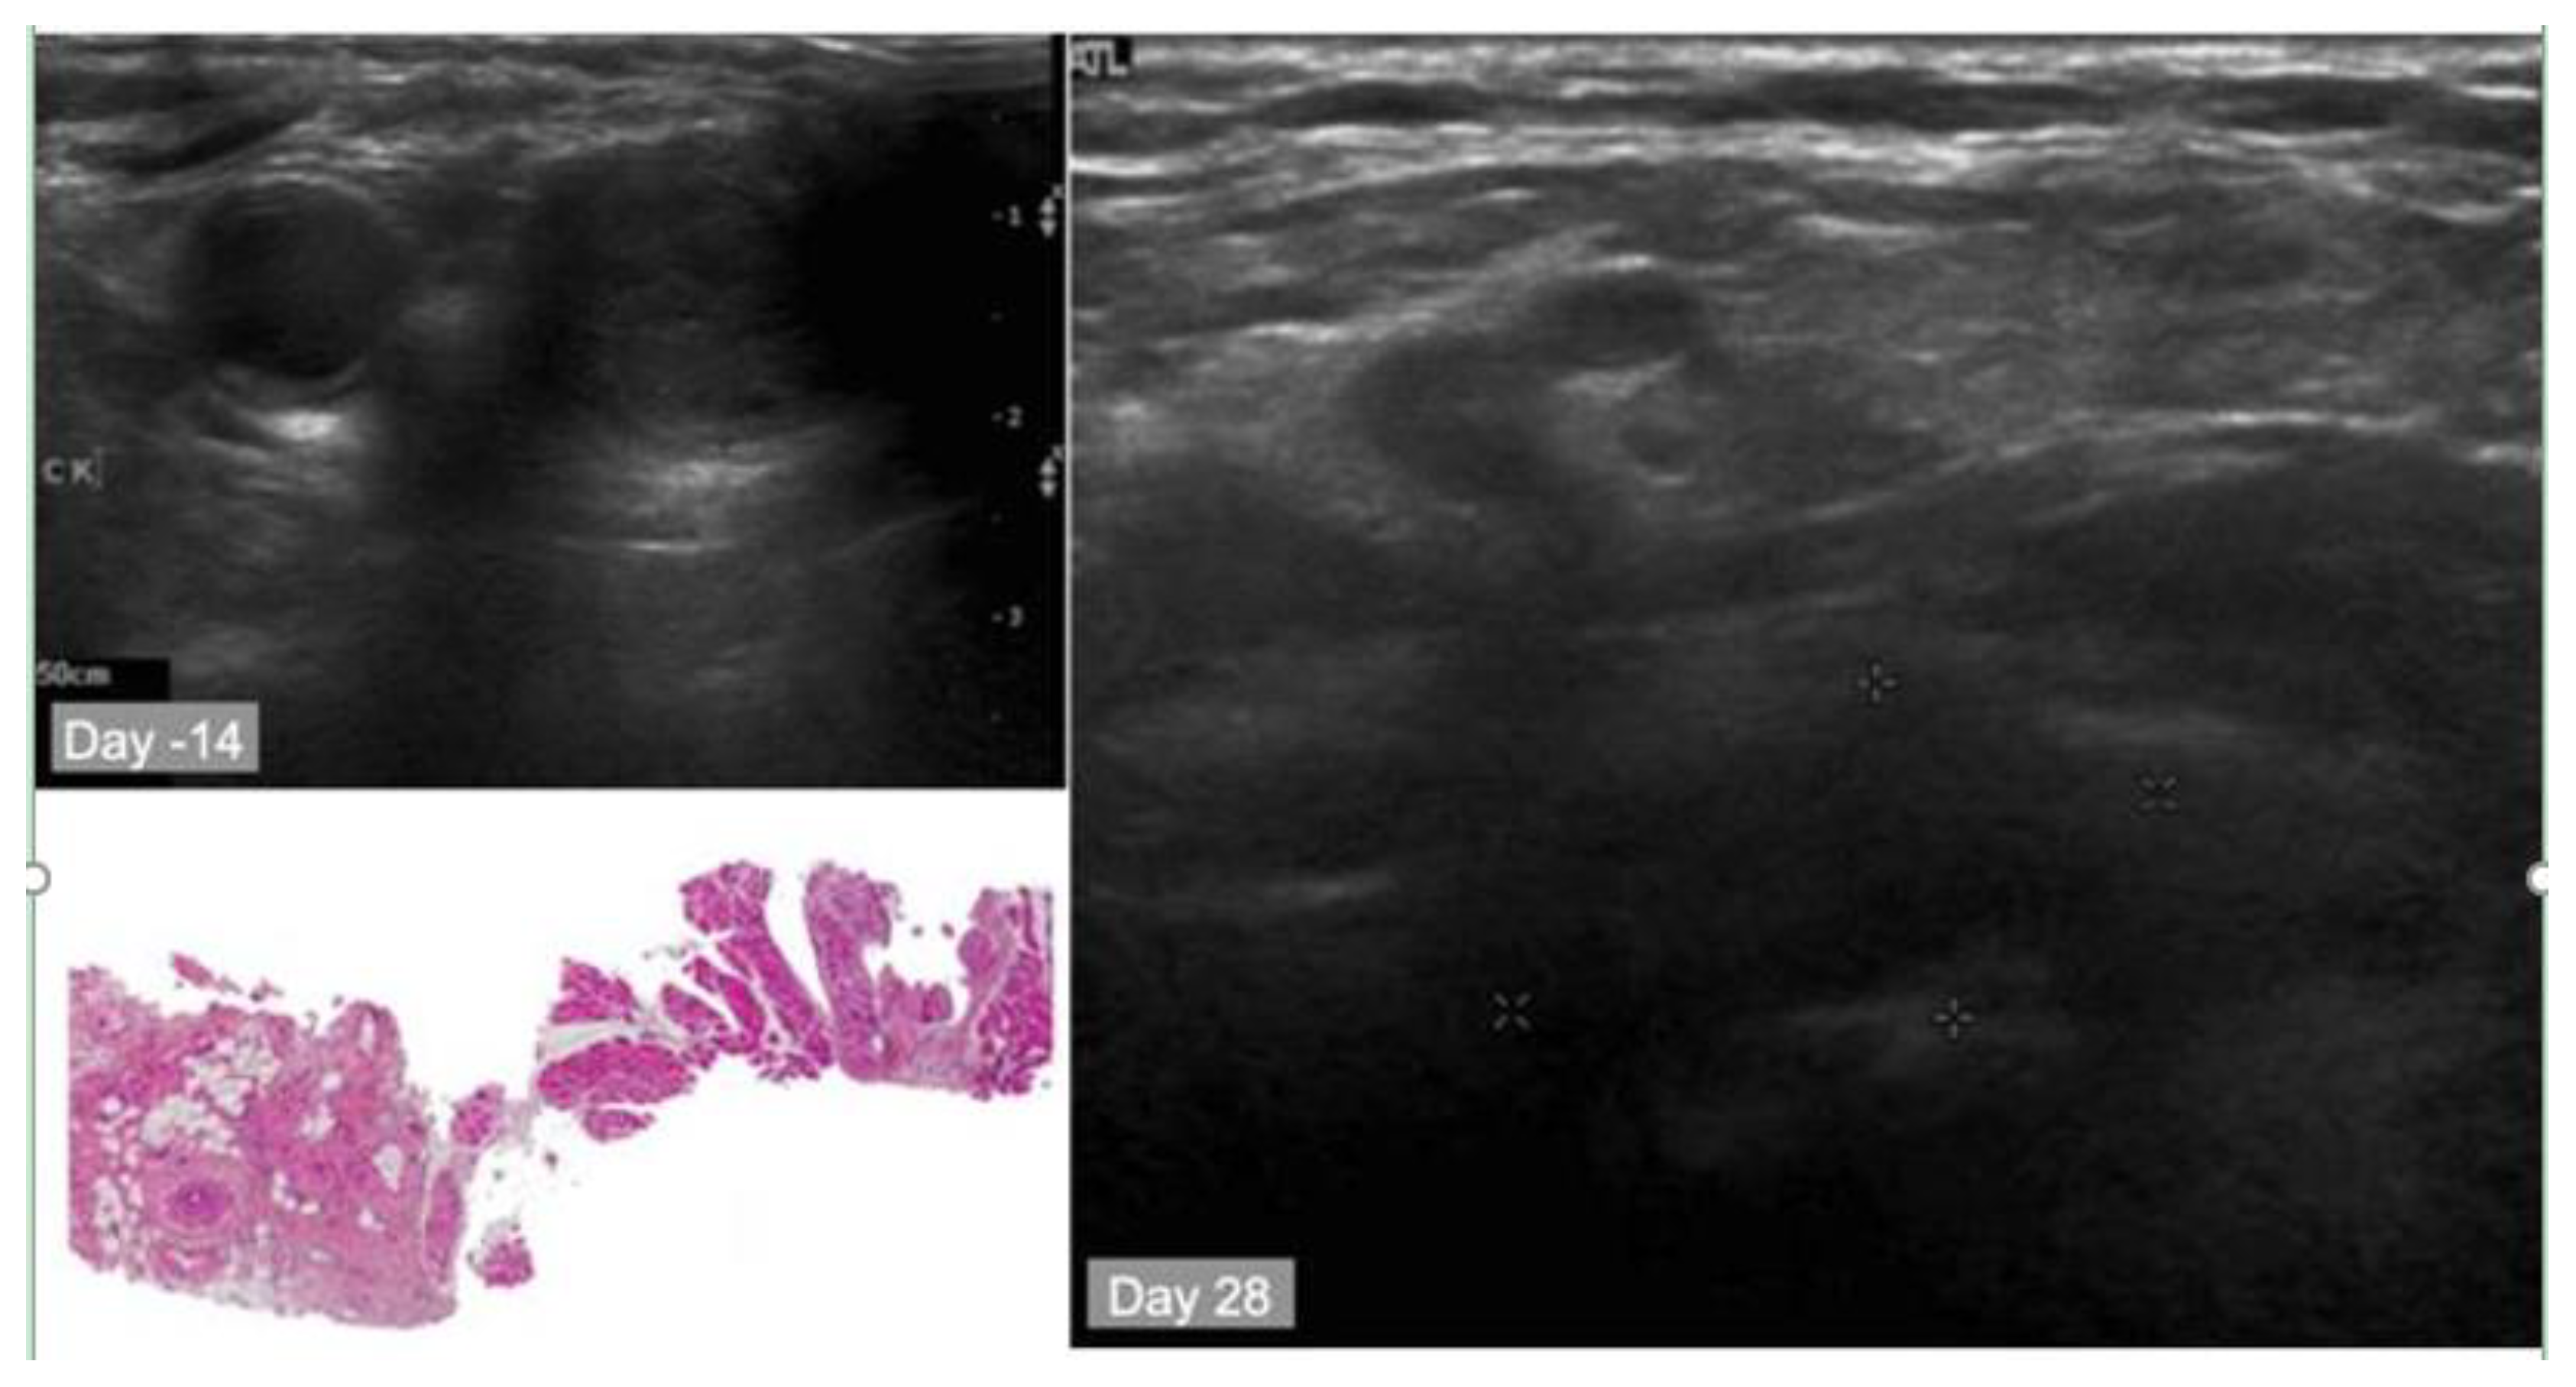

10.1. Summary of the First-in-Human PCI Trial

10.2. Case Study

- Sultan, A.A.; Jerjes, W.; Berg, K.; Hogset, A.; Mosse, C.A.; Hamoudi, R.; Hamdoon, Z.; Simeon, C.; Carnell, D.; Forster, M.; et al. Disulfonated tetraphenyl chlorin (TPCS2a)-induced photochemical internalisation of bleomycin in patients with solid malignancies: A phase 1, dose-escalation, first-in-man trial. Lancet Oncol. 2016, 17, 1217–1229. [Google Scholar] [CrossRef]